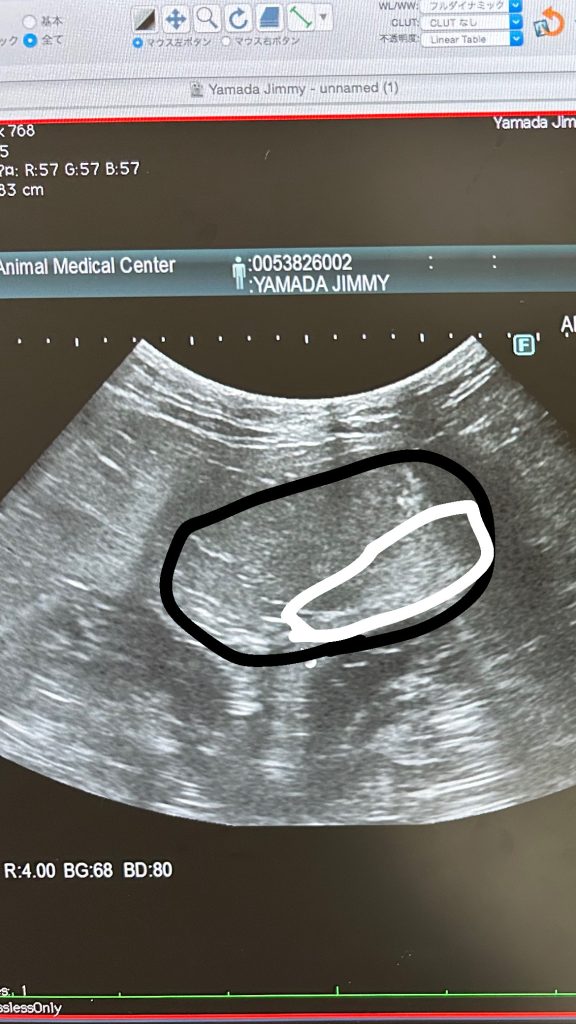

黒で囲んでるのが膀胱で白で囲んでるのが砂ね。前は結構な量の砂が溜まってたんやけど

今回はこんな感じに!先生曰く「結構減ってると思います。お尻のハゲ可哀想やけどハゲは今やってるケアを続けてもらったら大丈夫やと思います。」て言われましたー!

前回と膀胱内のおしっこの量が違うからちょっと写り方が見づらいけど💦

黒で囲んだとこ膀胱で合ってると思うw今日のエコーこ画像わかりにくくて多分、膀胱で合ってると思う!w